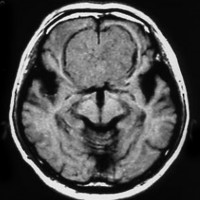

30代の女性に発生した髄膜腫です,一見すると松果体細胞腫と見分けはつきません。右の画像に見られるように典型的な中脳水道狭窄を生じていました。

軽度の閉塞性水頭症もありますが,頭痛も無く無症状なので経過を観察しました。髄膜腫だと診断できるのは,右の画像で見られるようにガレン大静脈が右側に偏っているからです。松果体細胞腫の場合は,ガレン大静脈は上方に変位します。